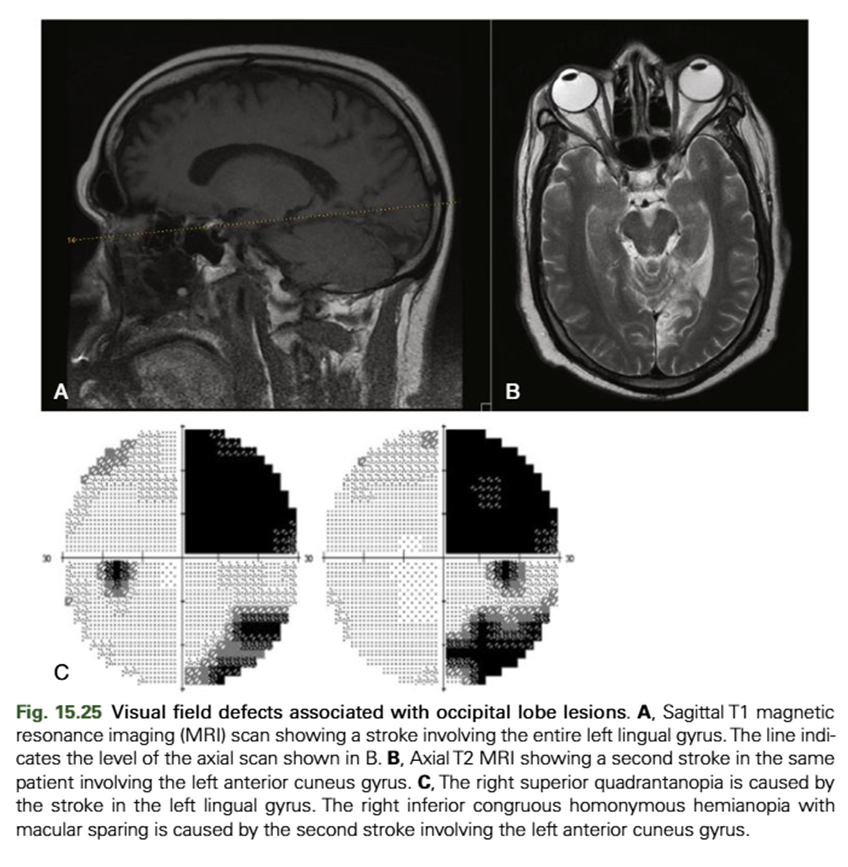

what would damage above the calcarine fissure + below the calcarine fissure result in

Damage above the calcarine fissure (Cuneus) → loss in inferior visual field

Damage below (Lingual gyrus) → loss in superior visual field

explain the effects of an occipital lobe lesion (4)

vertical midline is obeyed - post-retinal

if affecting R visual field in both eyes - will be affecting L part of brain and VV

affecting superior visual field - so inferior retinal fibers will be affected (lingal gyrus) and VV

R/L homonymous quadrantanopia